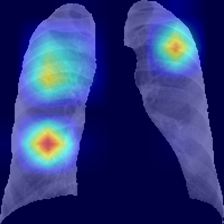

III-E Identification of the areas of significant interest for the classification

The areas of significant interest used by the CNN for discrimination purposes are identified using a qualitative analysis based on a Gradient-weighted Class Activation Mapping (Grad-CAM) [38]. This is an explainability method that serves to provide insights about the manners on how deep neural networks learn, pointing to the most significant areas of interest for decision-making purposes. The method uses the gradients of any target class to flow until the final convolutional layer, and to produce a coarse localization map which highlights the most important regions in the image identifying the class. The result of this method is a heat map like those presented in Fig. 1, in which the colour encodes the importance of each pixel in differentiating among classes.

The regions of interest identified by the network, were analyzed qualitatively using Grad-CAM activation maps [38]. Results shown by the activation maps, permit the identification of the most significant areas in the image, highlighting the zones of interest that the network is using to discriminate. In this regard, Fig. 1, presents examples of the Grad-CAM of a control, a pneumonia, and a COVID-19 patient, for each of the three experiments considered in the paper. It is important to note that the activation maps are providing overall information about the behaviour of the network, pointing to the most significant areas of interest, but the whole image is supposed to be contributing to the classification process to a certain extent.

The second row in Fig. 1 shows several prototipical results applying the Grad-CAM techniques to experiment 1. The examples show the areas of significant interest for a control, pneumonia and COVID-19 patient. The results suggest that the detection of pneumonia or COVID-19 is often carried out based on information that is outside the expected area of interest, i.e. the lung area. In the examples provided, the network focuses on the corners of the XR image or in areas around the diaphragm. In part, this is likely due to the metadata which is frequently stamped on the corners of the XR images. The Grad-CAM plots corresponding to the experiment 2 (third row of Fig 1), indicates that the model still points towards areas which are different to the lungs, but to a lesser extent. Finally, the Grad-CAM of experiment 3 (fourth row of Fig 1) presents the areas of interest where the segmentation procedure is carried out. In this case, the network is forced to look at the lungs, and therefore this scenario is supposed to be more realistic and more prone to generalizing as artifacts that might bias the results are somehow discarded.

We stand on the fact that automatic diagnosis is much more than a classification exercise, meaning that many factors have to be had in mind to bring these techniques to the clinical practice. To this respect, there is a classic assumption in the literature that the associated heat maps –calculated with techniques such as Grad-CAM– provide a clinical interpretation of the results, which is unclear in practice. In light of the results shown in the heat maps depicted in Fig. 1, we show that experiment 1 must be carefully interpreted. Despite the high-performance metrics obtained in experiment 1, the significant areas identified by the network are pointing towards certain areas with no clear interest for the diagnosis, such as corners of the images, the sternum, clavicles, etc. From a clinical point of view, this is clearly biasing the results. It means that other approaches are necessary to force the network to focus on the lungs area. To this respect, we have developed and compared the results with two preprocessing approaches based on cropping the images and segmenting the lungs area (experiment 2 and experiment 3). Again, given the heat maps corresponding to experiment 2, we also see similar explainability problems to those enumerated for experiment 1. Reducing the area of interest to that proposed in experiment 2 significantly decreases the performance of the system due to the removal of the metadata that usually appear in the top left and/or right corner, and to the removal of areas which are of interest to categorize the images but have no interest from the diagnosis point of view. However, while comparing experiment 2 and 3, performance results improve in the third approach, which focuses on the same region of interest but with a mask that forces the network to see only the lungs. Thus, results obtained in experiments 2 and 3 suggest that eliminating the needless features extracted from the background or non-related regions improves the results. Besides, the third approach (experiment 3), provides more explainable and interpretative results, with the network focusing its attention only in the area of interest for the disease. The gain in explainability of the last method is still at the cost of a lower accuracy with respect to experiment 1, but the improvement in explainability and interpretability are considered critical to translate these techniques to the clinical setting. Despite the decrease in performance, the proposed method in experiment 3 has provided promising results, with an Acc of , BAcc of , GMR of and AUC of .

The COVID-Net has also demonstrated being a good starting point for the characterization of the disease. Indeed, the outcomes of the paper suggest the possibility to automatically identifying the lung lesions associated with a COVID-19 infection (see Fig.1) by analyzing the Grad-CAM mappings of experiment 3, providing an explainable justification about the way the network works. However, the interpretation of the heat maps obtained for the control class must be carried out carefully. Whereas the areas of significant interest for pneumonia and COVID-19 classes are supposed to point to potential lesions (i.e. with higher density and/or with different textures in contrast to controls), the areas of significant interest for the classification in the control group are supposed to correspond to a sort of complement, potentially highlighting less dense areas. Thus, not meaning the presence of any kind of lesion in the lungs.